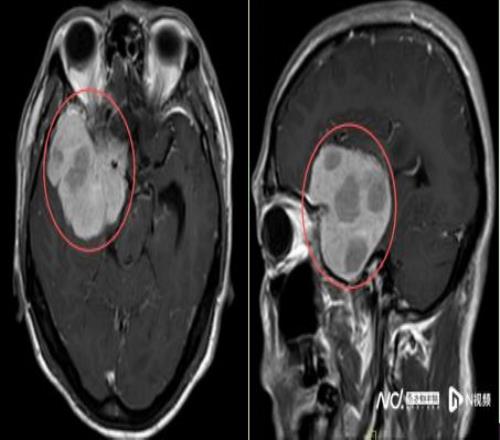

2025年10月起,他在跑步途中频繁在转弯处摔倒,偶尔还感觉一侧手脚乏力,起初并未放在心上。但随着摔跤次数不断增多,又无明显诱因地出现持续一周的头痛,他和家人终于警觉起来。同年11月中旬,陈叔家人带他在当地医院做了一次检查。MR结果如晴天霹雳:右额颞部蝶骨嵴占位病变,大小约5.5x6.6x5.8cm,考虑脑膜瘤。

鉴于肿瘤体积巨大、位置较深,考虑为右侧额颞蝶骨嵴内侧型巨大脑膜瘤,肿瘤突入垂体窝和斜坡,环绕颈内动脉及分支、视神经等重要结构,压迫脑干。手术难度是神经外科最复杂的手术之一,犹如刀尖上行走,且已出现进行性神经功能缺损症状:肢体乏力,视力受损,视物重影等,病情复杂、手术风险极高。